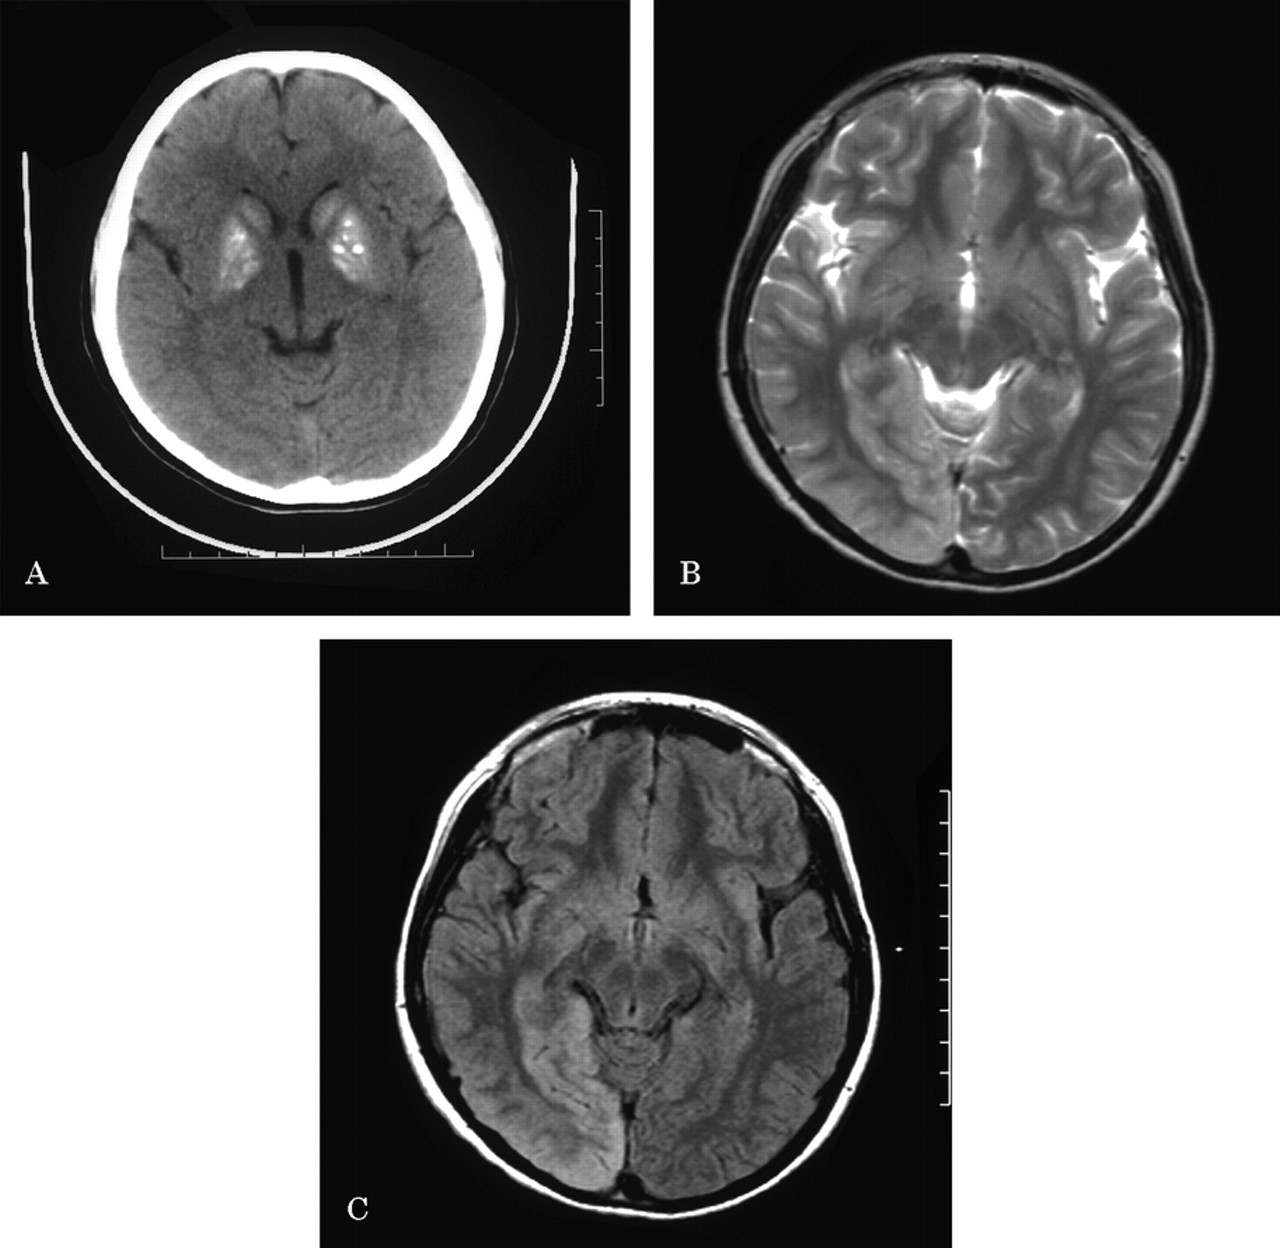

对称的基底节钙化与米拉一个9岁的孩子

一个9岁的男孩出现头痛、呕吐,左眼睛凝视偏差。在检查,左同向偏盲,水平眼球震颤,anisocoric学生指出。脑CT披露对称基底节钙化(图一个)。血液检查显示乳酸学术界。进一步的核磁共振显示右occipito-temporo-parietal皮质hyperintensities (图中,B和C)。肌肉活检显示ragged-red纤维,和遗传研究显示一个A3243G突变点,线粒体encephalomyopathy证实的诊断,乳酸酸中毒,strokelike症状(看见)。对称基底节钙化,脑局灶性病变不局限于血管的领土在一个年轻的病人需要进一步检查线粒体细胞病。1、2